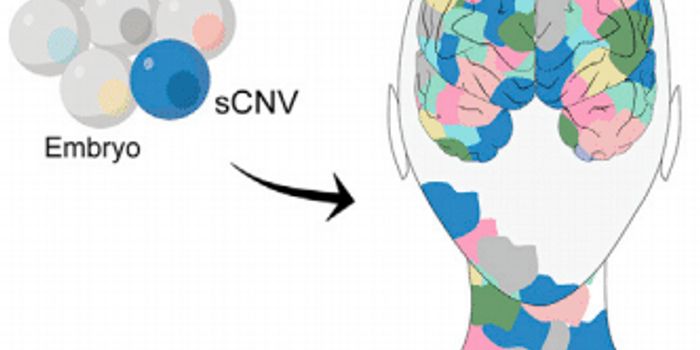

APR 05, 2024Genetics & GenomicsOnce thought of as a condition caused solely by external factors like injuries, infections, or oxygen deprivation ...